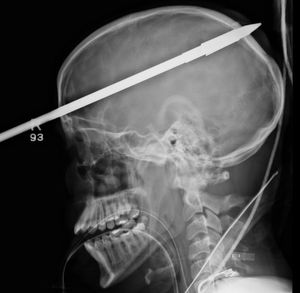

These X-rays show a miracle of a boy who survived 91cm harpoon fired accidentally by his friend. The spear entered the 16-year-old’s head just above his right eye, penetrated through his brain, before coming out the back of his skull. Miraculously, the spear missed all the vital blood vessels in the brain so non were damaged and he recovered the from incident!